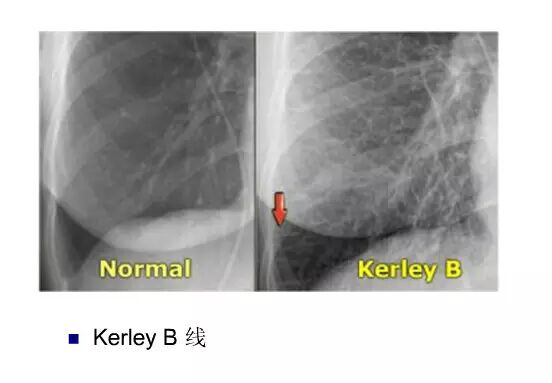

平片如何看心衰